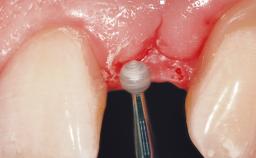

Late Flapless Placement of an Implant in a Maxillary Left Central Incisor Site

Soft Tissue Grafting Simultaneous

Soft Tissue Contour and Volume Slightly compromised